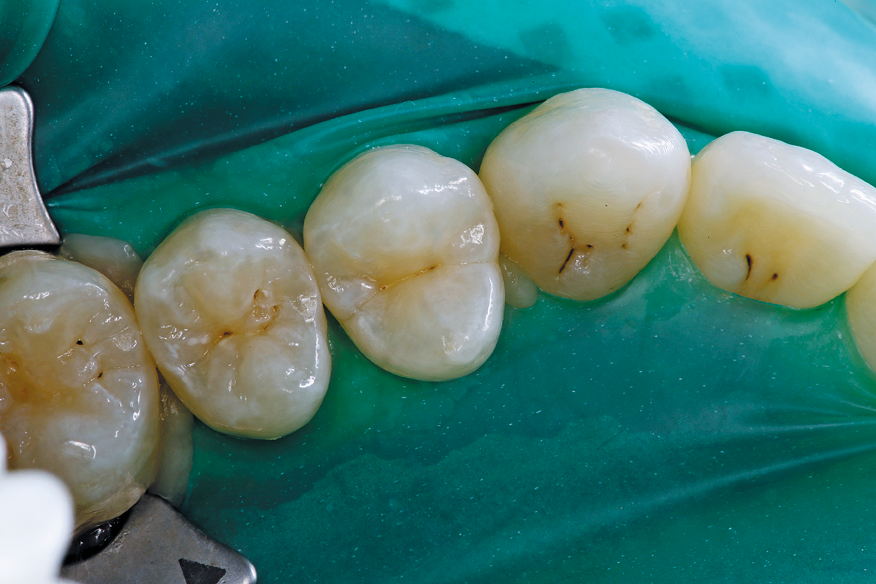

After caries removal and proper isolation (Isolite Systems), the tooth is restored with a highly filled flowable composite (G-aenial Universal Flow, GC America Inc.) (Fig. 2).

The patient was happy the carious tooth was restored in an efficient manner with zero discomfort and that a vast majority of healthy tooth structure was maintained (Fig. 3).